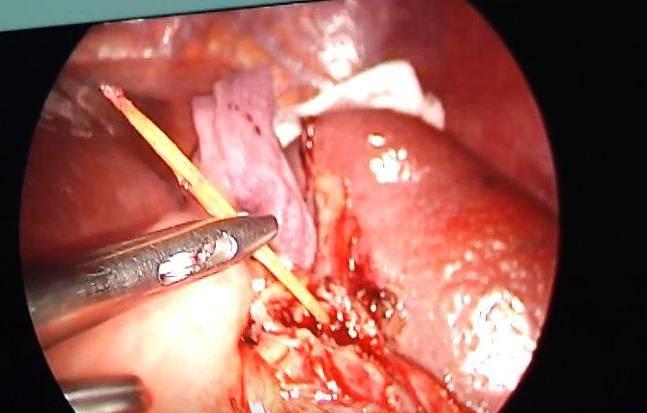

Cây tăm ghim thủng lá lách được chụp bằng ảnh nội soi. Ảnh: BSCC

Để nhanh chóng loại bỏ dị vật cùng các nguy cơ cho người bệnh, ê-kíp phẫu thuật quyết định tiến hành phẫu thuật nội soi để rút dị vật cho người bệnh.

Sau gần 2 giờ nỗ lực tìm kiếm cẩn thận vì lá lách vốn là một nội tạng chứa đầy máu, chỉ cần sơ sẩy là có nguy cơ xuất huyết ồ ạt phải chuyển mổ mở, cuối cùng các bác sĩ đã rút được dị vật là cây tăm xỉa răng dài 6cm.

Ngay tại thời điểm rút được cây tăm, dịch mủ đục vốn do cơ thể phản ứng với dị vật đã trào ra, đây cũng là một trong các lý do khiến ông H. đau âm ỉ liên tục 2 tuần. Tất cả phòng phẫu thuật đều phấn khởi khi lấy được dị vật an toàn được đồng thời vẫn giữ được lá lách toàn vẹn cho người bệnh.